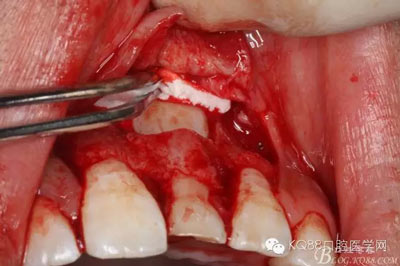

圖14.牙冠周?chē)鷿B血多,無(wú)法粘結(jié)托槽。位置也高,隨與家屬溝通,暫時(shí)保留乳Ⅰ。待21初步穩(wěn)定,再考慮正畸牽引

圖15.輕輕的把21牙冠牽引至乳Ⅰ根尖方向,并擺正牙冠位置。(拔苗助長(zhǎng))

圖16.牙冠上方覆蓋膠原蛋白膜

圖17.骨壁重新覆蓋回去